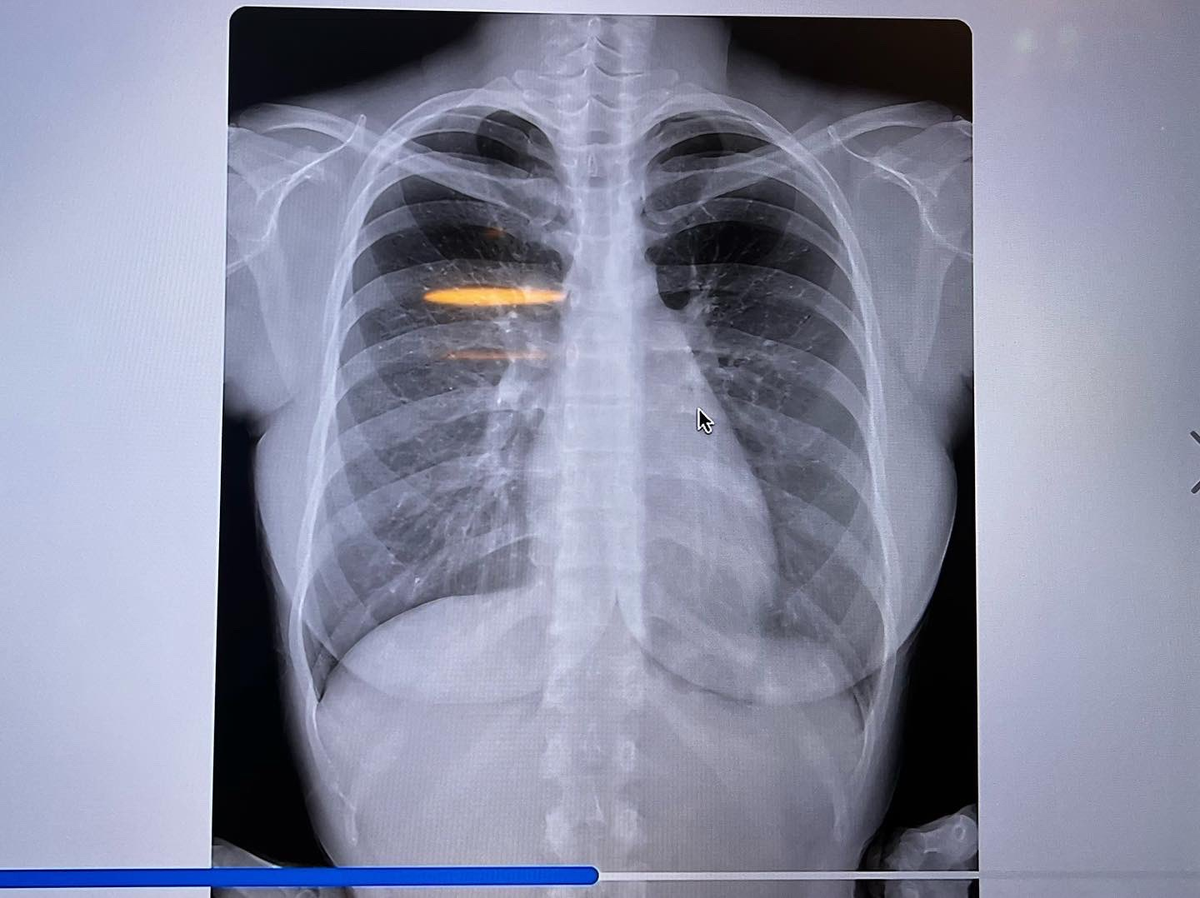

タレント、女優の鈴木ふみ奈(32)が14日、胸部レントゲン写真をツイッターに投稿した。

人間ドックを受診した際のもので、「私の胸部レントゲン!笑」の文言とともに正面・左右から撮影したものなど4枚を掲載。「これで私の胸が天然な事は証明できたのかな?」と〝加工なし〟を強調した。